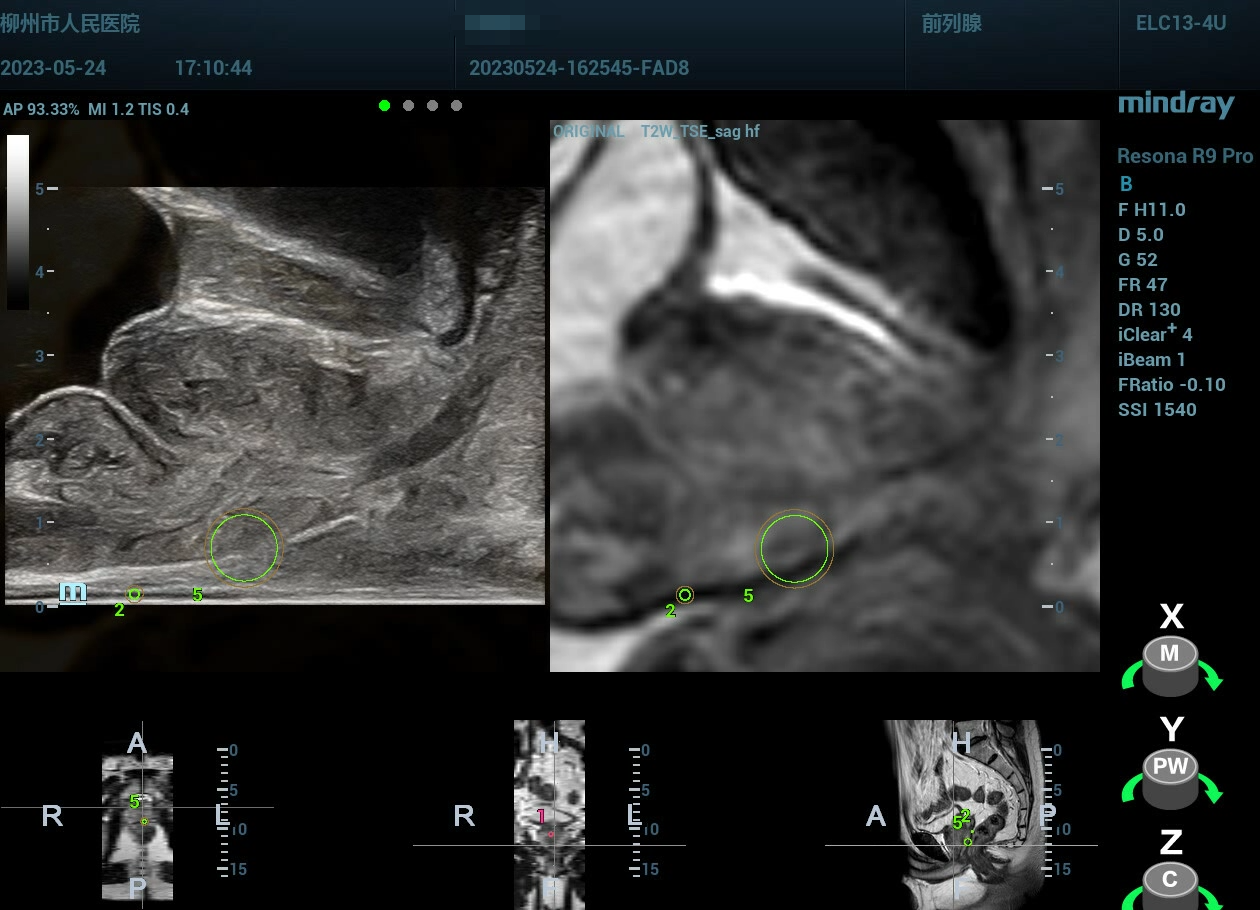

Q8:认知融合 VS 软件融合?

多模态影像(多模式TRUS+mp-MRI )的靶向前列腺穿刺活检术在发现有临床意义前列腺癌、避免过度诊断方面具有明显的优势。

image.png

1686649675457.jpg

1686649503154.jpg